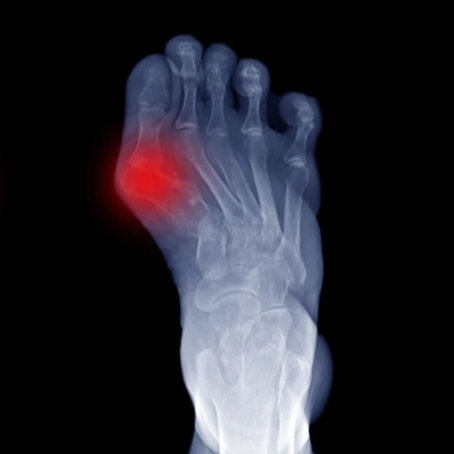

A bunion is a painful deformity of the inner foot bone. In this progressive condition, the bump located behind the big toe enlarges to the point that the toe is forced to deviate and press into the neighboring second toe. One of the primary culprits to bunions is the tapered toe box present in most footwear.